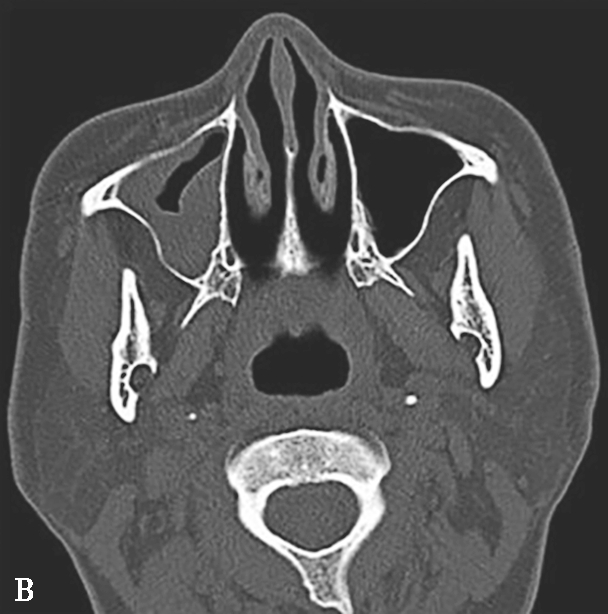

该病多发生于上颌窦和筛窦,其次为蝶窦,额窦罕见。早期表现为单侧鼻腔、鼻窦黏膜和软组织增厚,但无特异性,应密切结合临床考虑;Silverman等提出上颌窦周围脂肪间隙软组织浸润为该病较早的征象;典型表现为鼻窦内充以软组织影,窦壁及邻近颅面部骨质可出现广泛骨质破坏,但无窦腔变形,窦腔内一般无钙化;广泛侵犯眼眶、颞下窝、翼腭窝、硬腭、颅面部软组织等邻近结构,严重者可侵犯颅内,出现脑膜炎、脑炎、脑脓肿、脑梗死等(图1-3-23A、B)。

图1-3-23 急性侵袭性真菌性鼻窦炎

A、B.横断面、冠状面CT骨窗,示双侧蝶窦、后组筛窦软组织影,密度不均,窦壁骨质硬化伴局部骨质破坏,累及双侧圆孔、翼管;C~E.MRI横断面T 1 WI、T 2 WI、T 1 WI+FS+C,示双侧蝶窦、后组筛窦内混杂长T 1 、长T 2 信号,窦腔内见斑片状短T 1 、短T 2 信号影,增强扫描边缘强化,前颅底脑膜增厚强化